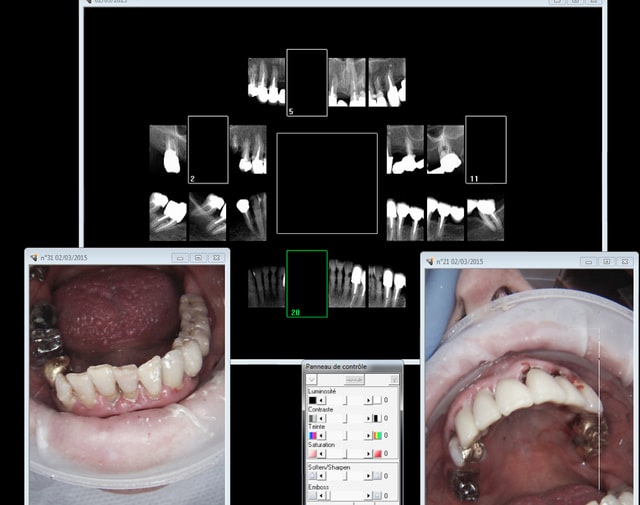

Tu t'occupes de santé publique, hein ? Alors je vais t'expliquer comment ca se passe à long terme sur le terrain grace à la merveilleuse nomenclature de ce système collectiviste de merde :

Endo pourries à un tarif de merde- coiffes...... extractions........ bridge ......... extractions- complet immédiat.

Tu es sur que tu sers à quelque chose ? quelle réussite ! -))))

Big up pour la CCAM ultra moderne ( bridges) qui va dans le bon sens !

Ca fait toujours son effet un complet immédiat, un plaisir à gérer pour le praticien et le patient !

Apparement ,nos tetes pensantes ont décidés qu'il était plus simple

de leur donner le DROIT d'avoir du 4 à 4 céramisés (payés 8000 euros pour les 2 arcades) plutot que le DEVOIR d'utiliser une brosse à dent souples à 4 euros .